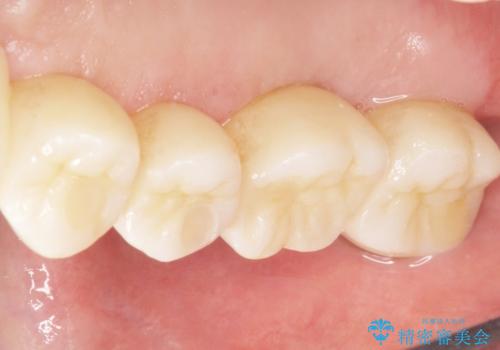

奥歯でしっかりと咬むことができるようになり、喜んで頂けました。

治療終了後には「なんでも食べられるようにしてくれてありがとうございます!」とおっしゃって下さいました。

クラウンの種類:ベレッツァクラウン